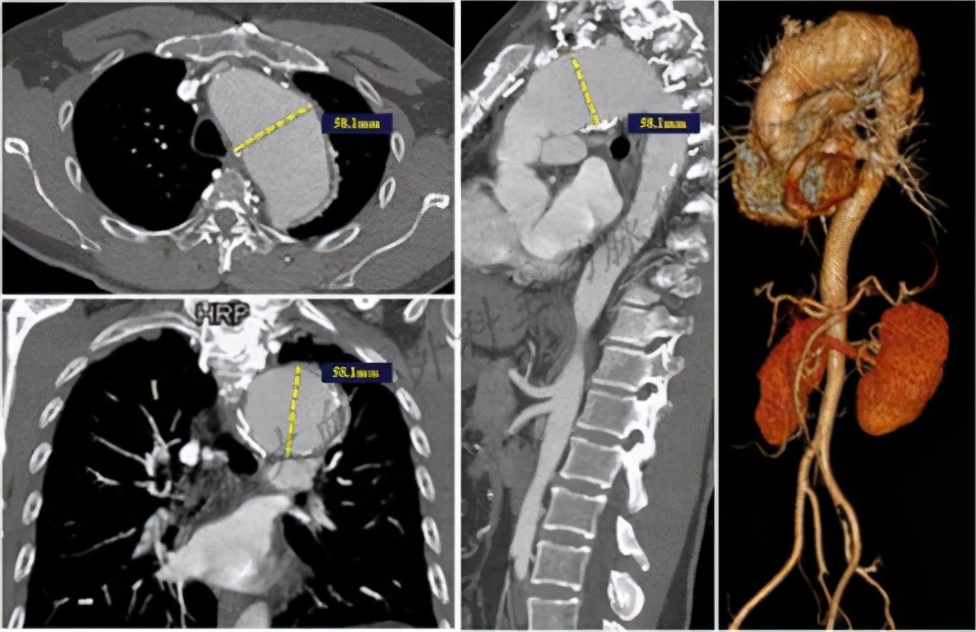

此次因“胸痛1天”,吴先生再次就诊于四川大学华西医院,增强CT示:A型主动脉夹层近端修复术后,主动脉弓部巨大动脉瘤形成,最大直径达58.1mm。吴先生主动脉弓部病变亟需解决,否则远期发生主动脉夹层甚至自发性破裂的风险较高。